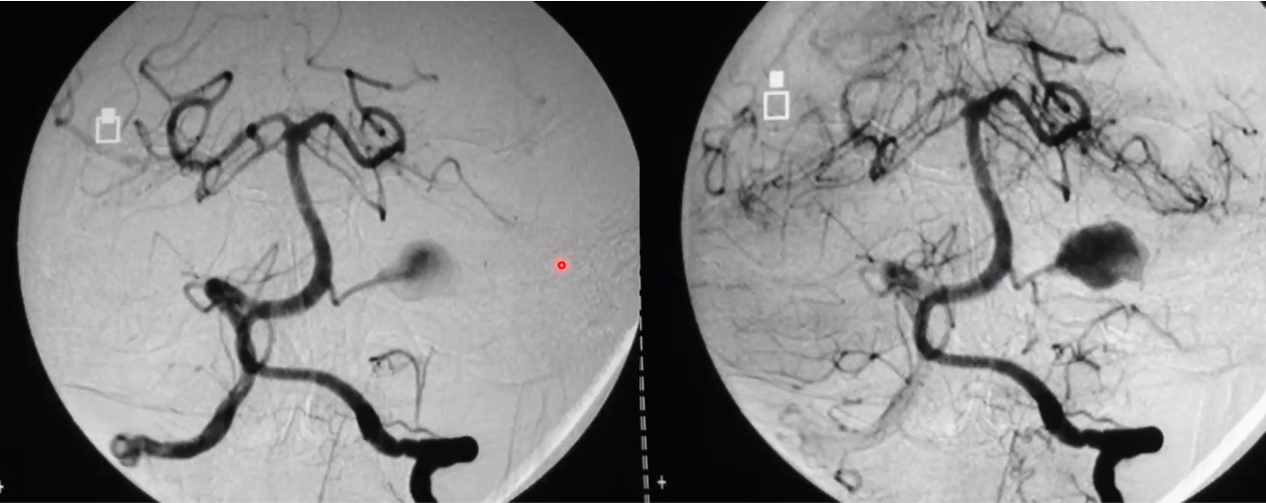

JNA (also known as juvenile angiofibroma)

involes pterygopalatine fossa

consider preop embolization